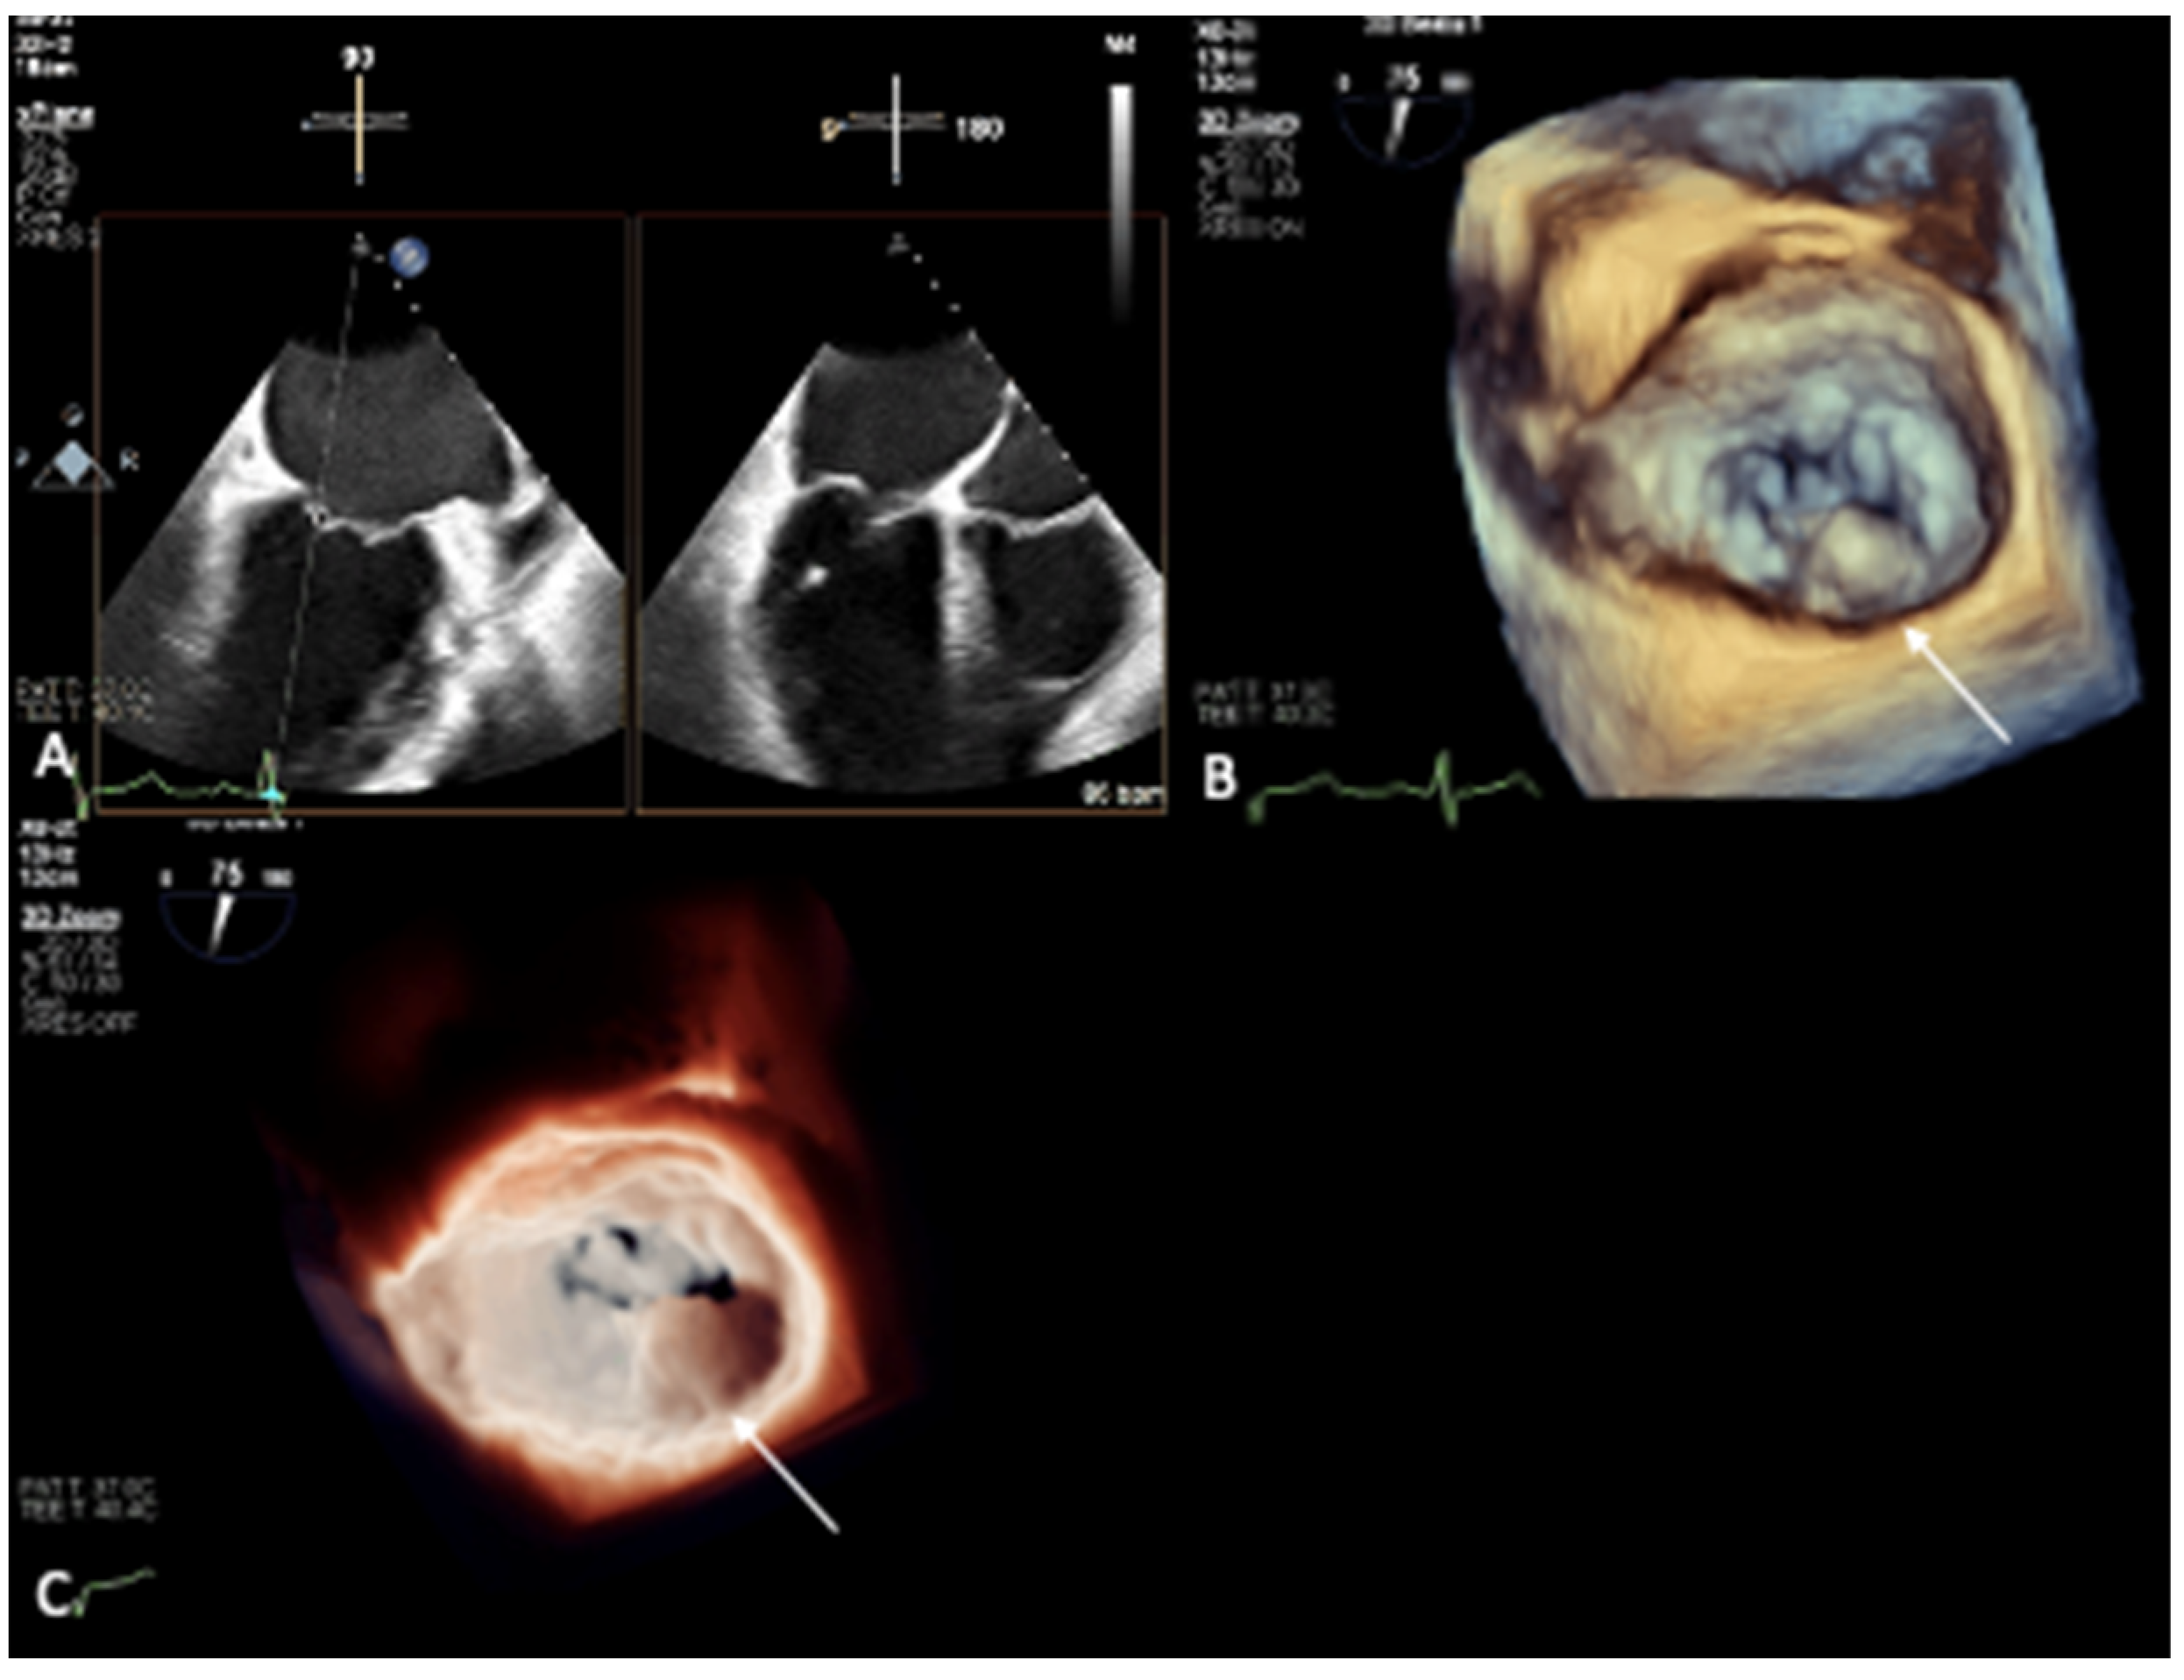

2. Mitral Annular Calcification Imaging

3. Novel 3D Echocardiographic Technique for MAC

4. Maximal Intensity Projection Map Applications

- Prandi, F.R.; Anastasius, M.O.; Zhang, L.; Tang, G.H.; Moreno, P.R.; Romeo, F.; Barillà, F.; Sharma, S.; Kini, A.; Lerakis, S. Novel Three-Dimensional Transesophageal Echocardiographic Method for Mapping Mitral Annular Calcifications. J. Am. Soc. Echocardiogr. 2022, 35, 1004–1005. [Google Scholar] [CrossRef] [PubMed]

- Prandi, F.R.; Dangas, G.D.; Kini, A.; Romeo, F.; Suleman, S.; Khera, S.; Tang, G.H.; Sharma, S.; Lerakis, S. Intraprocedural Mapping of the Mitral Calcium for Positioning and Deployment of Transcatheter Valve-in-Mitral Annular Calcification. JACC Cardiovasc. Interv. 2022, 15, 2341–2343. [Google Scholar] [CrossRef] [PubMed]